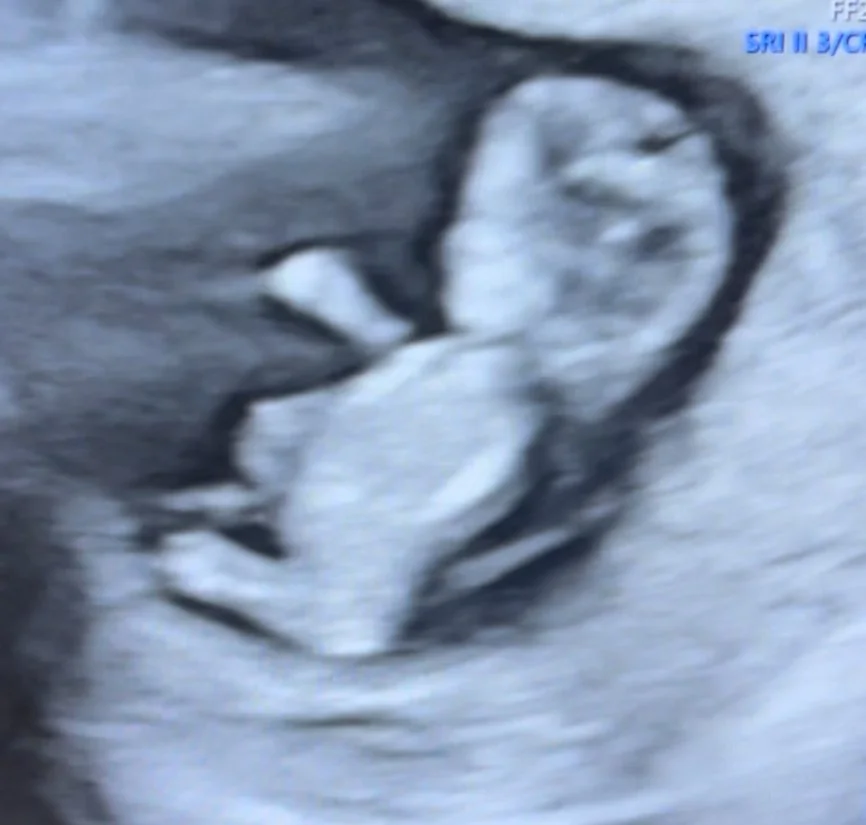

I’m currently 21 weeks pregnant, with only four more months to go. Baby’s kicks are getting stronger. It feels like pure magic…. tiny punches and kicks from this little soul growing inside me.

10 week ultrasound. Fisrt time we got to see him!